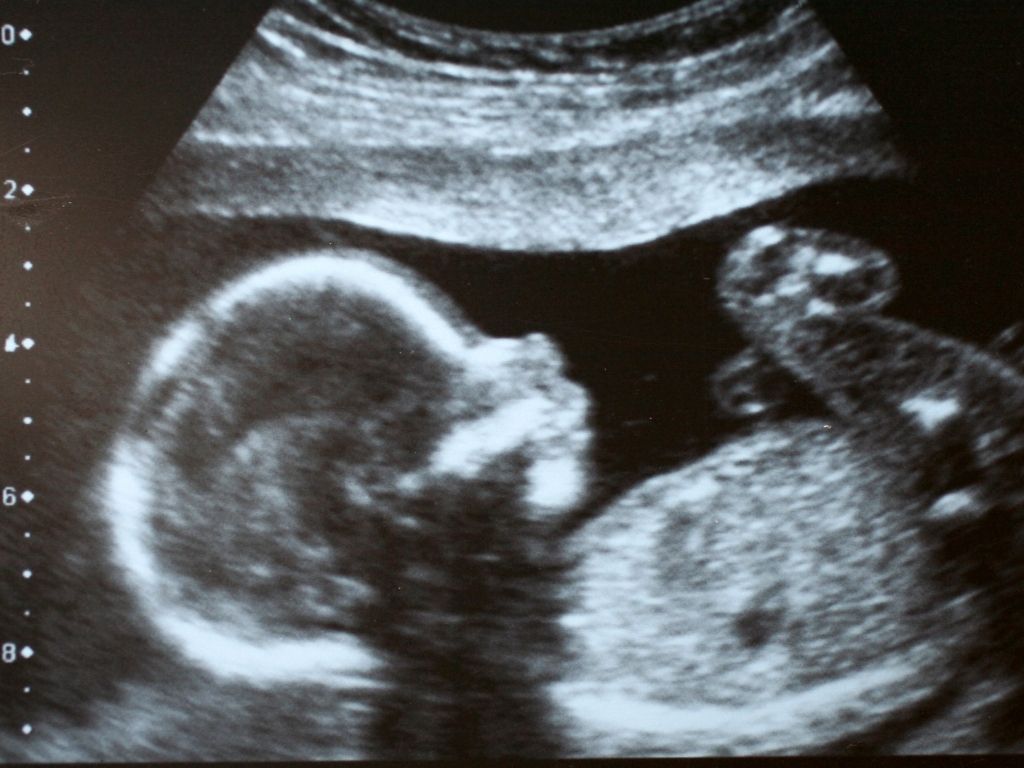

Ультразвукове дослідження – це один із найважливіших і найемоційніших етапів вагітності. Воно дозволяє не просто побачити дитину, а впевнитися, що вагітність розвивається правильно, усі органи формуються в нормі, а мама та малюк перебувають у безпеці.

У клініці Medibor ми проводимо УЗД вагітності на сучасному обладнанні, яке забезпечує високу деталізацію зображення та максимальну точність оцінки розвитку плода.

Найдетальніше скринінгове УЗД: детально оглядається мозок, серце, внутрішні органи, кінцівки, плацента.